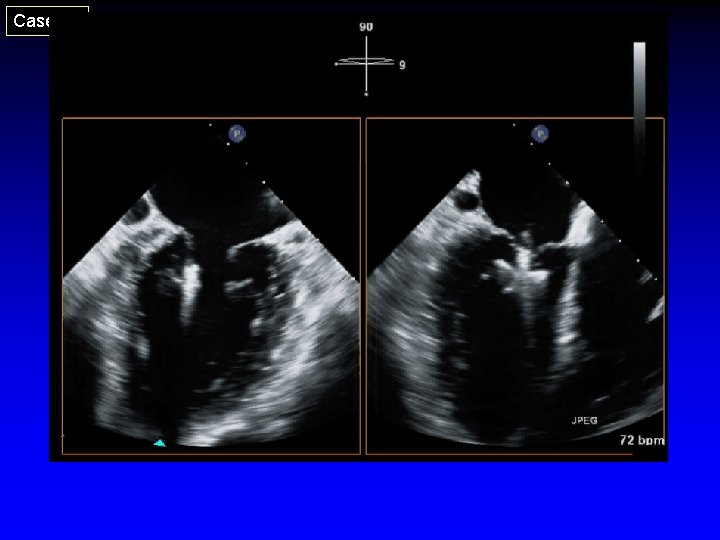

Case 36